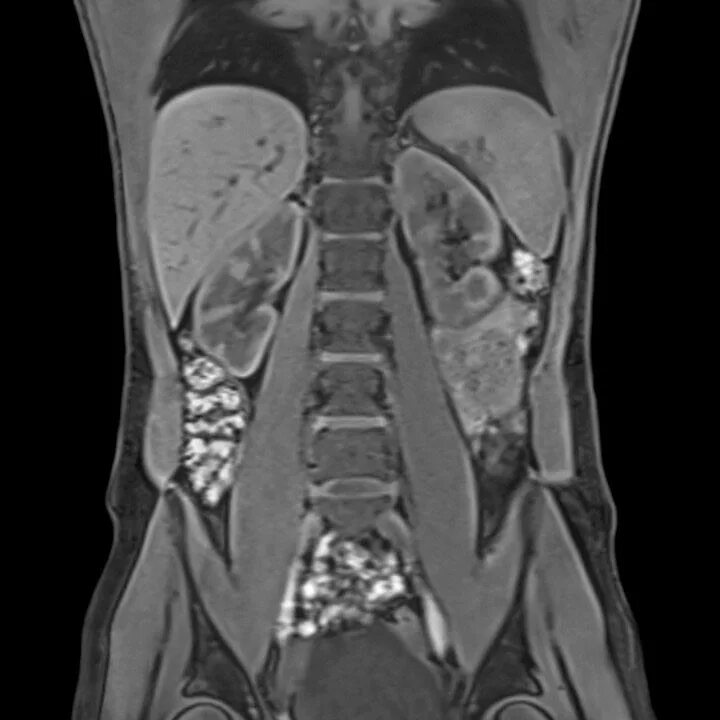

Что входит в мрт забрюшинного пространства